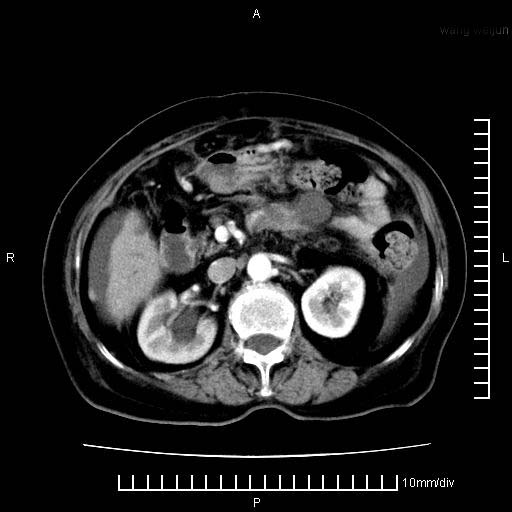

标题: CT28280:腹部增强:女性,80岁

上腹疼痛月余,外院核磁诊断胰腺癌。现临床示右下腹可明显触及包块,可片子上怎么没有看到?

胰腺结构模糊,胰尾部见囊性包块,周围脂肪密度增高,左肾前筋膜增厚,胸水、腹水。不符合胰腺ca伴腹膜腔转移。考虑胰腺炎伴假性囊肿形成、胸腹腔积液。

右肾盂囊肿。

1)考虑胰腺癌并胰腺假性囊肿形成。2)肝内低密度灶,不排除转移。3)右肾盂积水。4)腹水。5)右侧胸腔积液并右肺下叶部分膨胀不全。